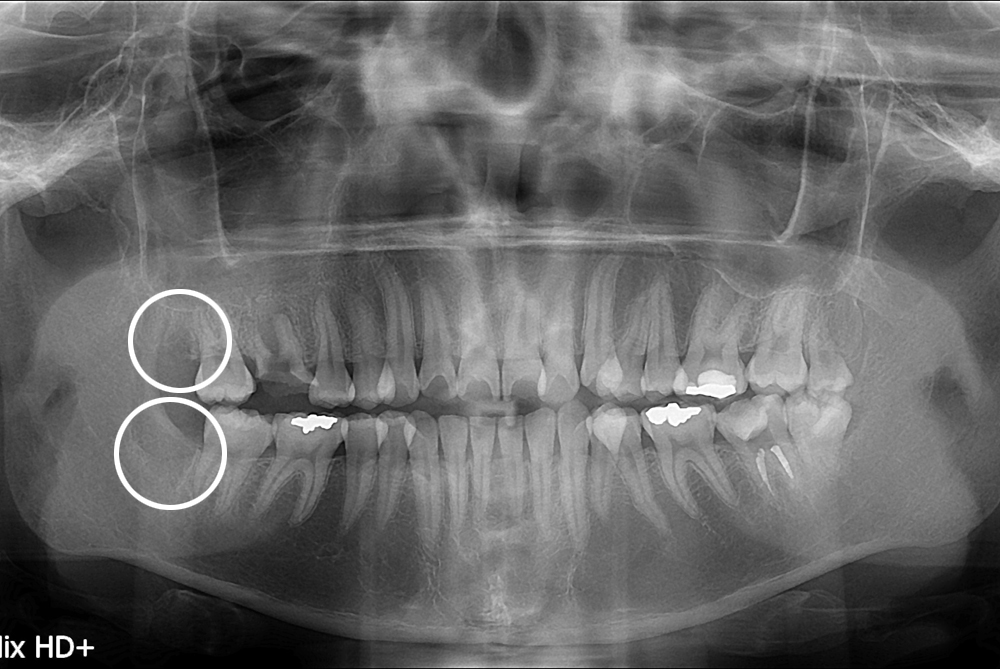

치료후 : 2017-10-11

세종치과는 구강악안면외과학 박사이신 원장님이 발치하는 치과입니다.